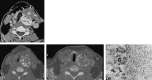

A 74-year-old man with a history of a chondroid lesion of the larynx noted an enlarging neck mass. Axial CT showed a large expansile lesion arising from the left thyroid cartilage. Multiple rings and arcs with relatively intact cortex indicated a chondroid lesion. Irregularity of the anterolateral margin abutted a prominent soft-tissue component. The specimen obtained from fine needle aspiration was suggestive of a malignant fibrous histiocytoma. After further resection, the final diagnosis was dedifferentiated chondrosarcoma. A new soft-tissue component or rapid growth of the mass can be indicative of a diagnosis of dedifferentiated chondrosarcoma.